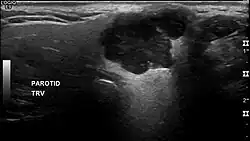

In terms of imaging studies, ultrasound can determine and characterize superficial parotid tumors. Certain types of salivary gland tumors have certain sonographic characteristics on ultrasound.[6] Ultrasound is also frequently used to guide FNA or core needle biopsy.

- ^ Białek EJ, Jakubowski W, Karpińska G (September 2003). "Role of ultrasonography in diagnosis and differentiation of pleomorphic adenomas: work in progress". Archives of Otolaryngology–Head & Neck Surgery. 129 (9): 929–933. doi:10.1001/archotol.129.9.929. PMID 12975263.